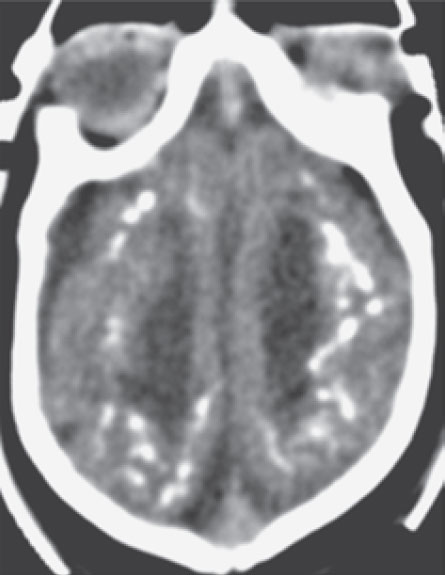

Signs of damage

Inside the brain of this infant born with microcephaly (and with suspected Zika virus infection), researchers spotted bright white spots and streaks of calcifications, areas that represent damaged tissue. Researchers found similar damage in the 22 other microcephalic infants examined.

- Zika infection may throw a wrench in babies’ brain development (rather than outright destroying cells). CT scans of 23 infants with microcephaly (all suspected of having Zika infection) reveal widespread lack of the fatty tissue that insulates nerve cells, researchers report April 6 in the New England Journal of Medicine. Without this insulation, messages can’t zip quickly between brain cells.